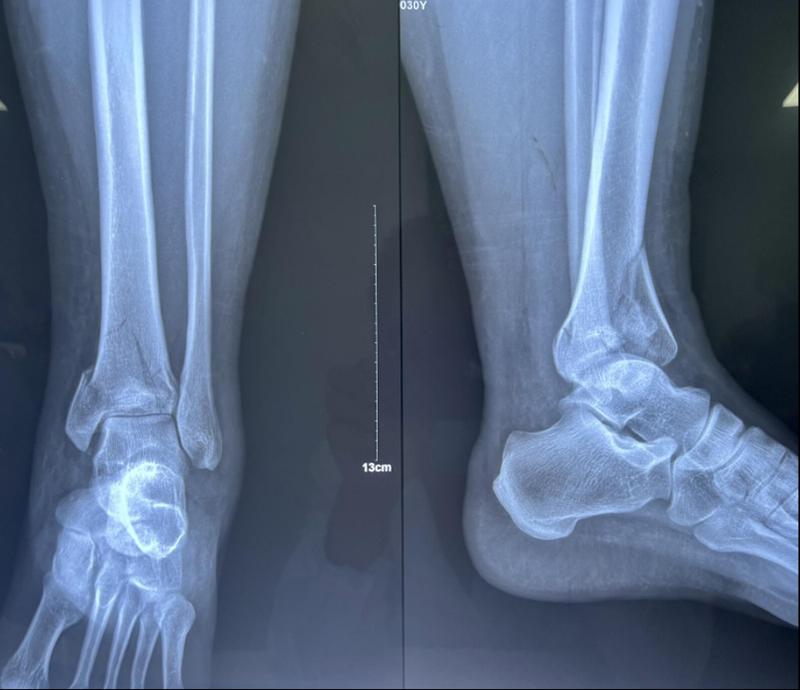

诊断:左胫骨平台后柱骨折,后交叉韧带撕脱骨折,左踝关节pilon骨折3型。

图8 Pilon骨折3型

术中资料:切口与术中C-臂检测